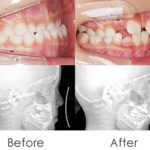

「将来は外科矯正が必要」と言われた受け口の女の子。

上顎の成長促進・過蓋咬合の改善・機能訓練を同時にスタートしました。

1年後(小3 → 小4)

かみ合わせもお顔立ちも大きく改善。

成長のピークに合わせて上顎をもう一度拡大し、前歯のかみ合わせをさらに安定化。

成長期の波に合わせることで、より調和の取れた横顔へ。

治療開始から6年後。

治療終了後2年経っても、安定したかみ合わせと自然な横顔をキープ。

2年生で外科矯正と言われた受け口も、4年生になる頃にはすでに「バランスの良いお顔立ち」に。のびのびと成長期を過ごすことができました。